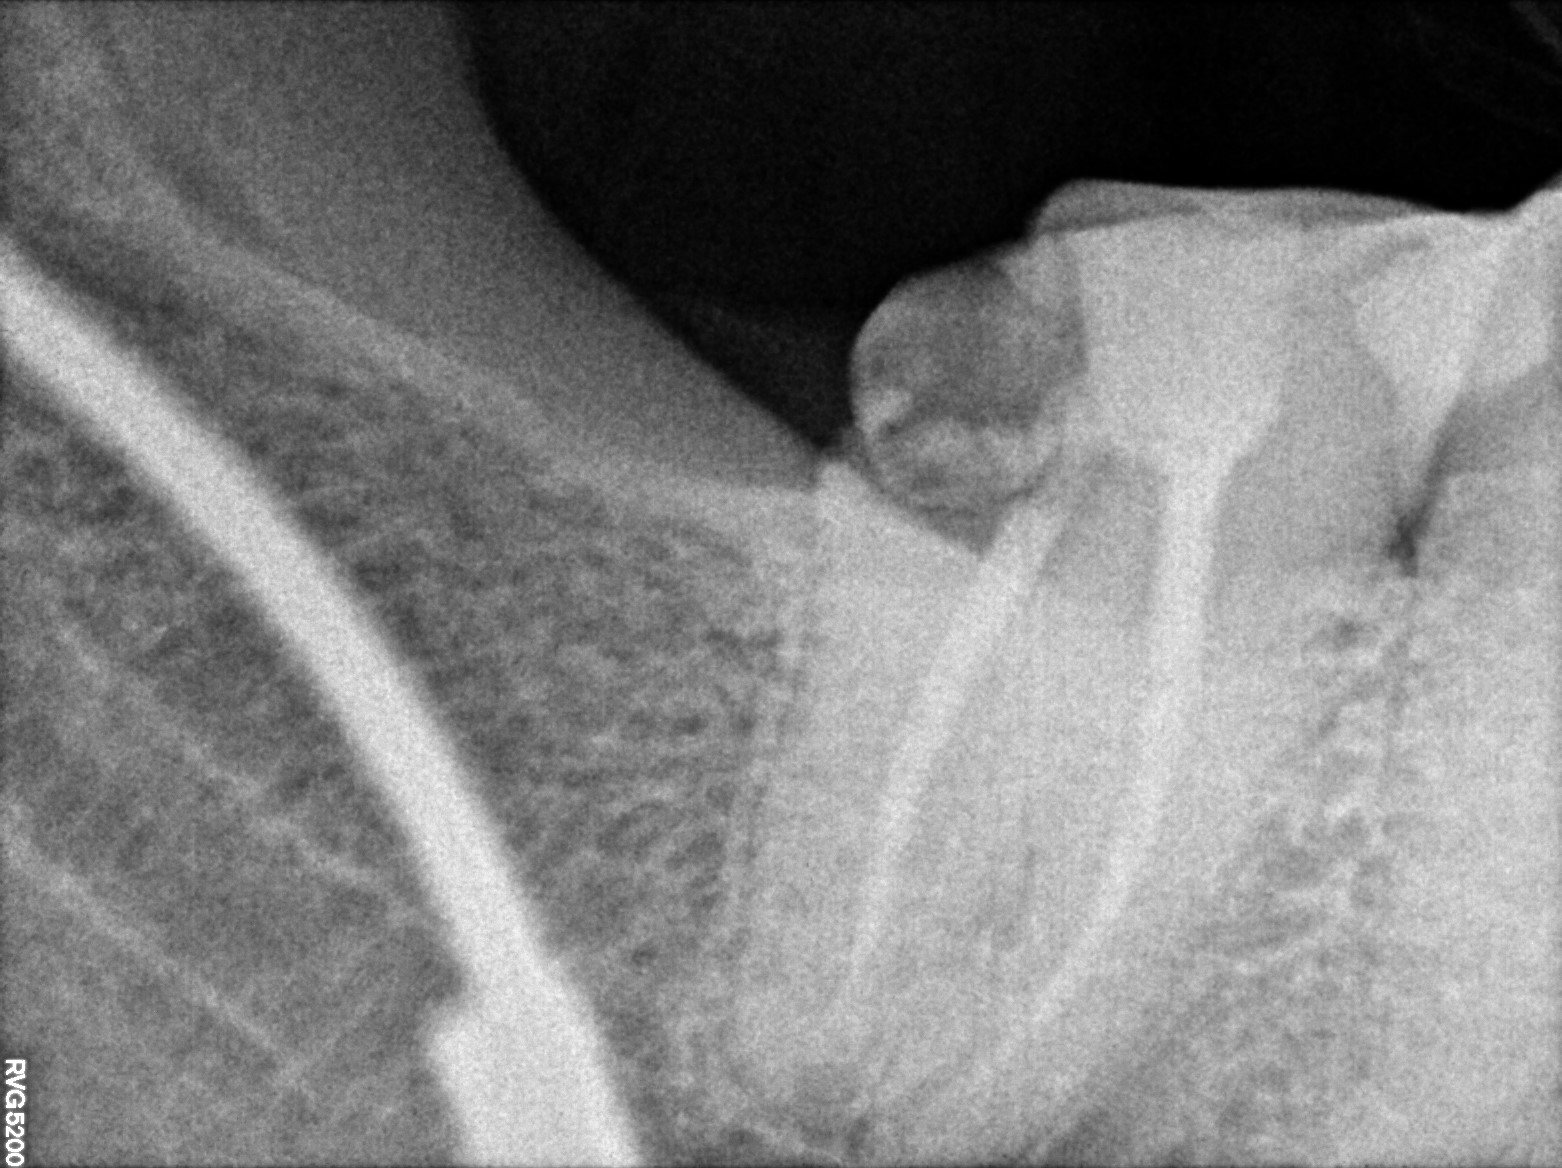

Dental Radiographs FHIR: DocumentReference · LOINC 24641-7

xray_1747063643_0.jpg

24641-7